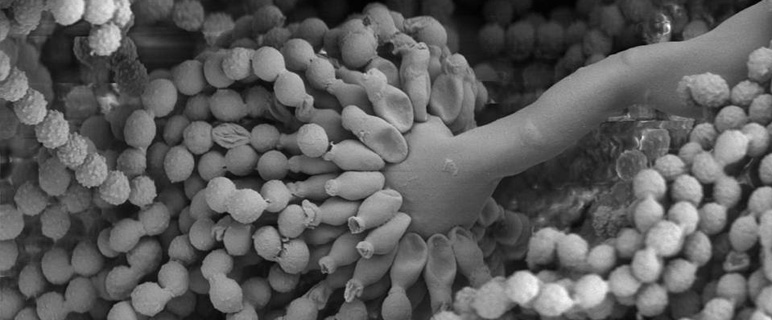

Aspergillus fumigatus ist ein Schimmelpilz, der insbesondere für Personen mit einem geschwächten Immunsystem zur Gefahr werden kann. Die durch Aspergillus hervorgerufenen Erkrankungen werden Aspergillosen genannt und könnten trotz rechtzeitiger Diagnose und Therapie tödlich verlaufen. Ein Grund für die hohe Sterblichkeitsrate ist, dass der Pilz gegenüber herkömmlichen Antimykotika, also Medikamenten zu Behandlung von Pilzinfektionen, Resistenzen bildet. Für eine erfolgreiche Behandlung einer Infektion mit Aspergillus fumigatus müssen daher dringend neue Behandlungswege gefunden werden. Seit 1998 forscht mit Unterstützung des Wissenschaftsfonds (FWF) und der Österreichischen Nationalbank (ÖNB) die Innsbrucker Arbeitsgruppe unter der Leitung von ao. Univ.-Prof. Dr. Hubertus Haas am Eisenhaushalt der Schimmelpilze. Seit 2006 ist auch Mario Gründlinger in der Forscher:innengruppe tätig. In seiner molekularbiologischen Forschungsarbeit hat er weitere wichtige Erkenntnisse über den Aufbau und das Wachstum des Schimmelpilzes herausgefunden und damit einen weiteren Beitrag zur Entwicklung neuer Diagnose- und Therapiemöglichkeiten geleistet. Gründlinger konnte mittels internationaler Zusammenarbeit mit englischen und spanischen Arbeitsgruppen aufzeigen, dass es zwischen der Ergosterol- und der Siderophore-Biosynthese des Pilzes eine wechselseitige Verbindung gibt. Für seine Forschungsergebnisse, die Ende letzten Jahres im renommierten PNAS Journal der „National Academy of Sciences“ der USA erschienen sind, erhielt der Jungforscher den Österreichischen Mikrobiologie Preis 2012. Die Österreichische Gesellschaft für Hygiene, Mikrobiologie und Präventivmedizin (ÖGHMP) verleiht den Preis alle zwei Jahre. Der von der Mycosafe Diagnostics GmbH gesponserte Preis wurde am 23. Mai an zwei Preisträger in Salzburg verliehen. (Weiterer Preisträger: Dip.-Ing. Gerald Posch, Universität für Bodenkultur Wien)

Die Forschungsgruppe rund um Prof. Haas hatte bereits herausgefunden, dass das Siderophorsystem, ein pilzspezifischer Eisenaufnahmemechanismus, essentiell für die Virulenz des Schimmelpilzes ist. Gelingt es, die notwendige Eisenzufuhr zu stoppen, dann kann das Wachstum des Pilzes stark eingeschränkt werden. Damit wurde bereits ein wichtiges Target für die Entwicklung von Medikamenten zur Behandlung einer Aspergillose gefunden. Bereits bekannte antifungale Mittel wie Azole oder Amphotericin B, die in der herkömmlichen Therapie eingesetzt werden, zielen allerdings auf die pilzliche Ergosterolbiosynthese ab. „Jetzt konnten wir herausfinden, dass diese zwei Biosynthesewege, also für Siderophore und Ergosterol, direkt über den gemeinsamen Metaboliten Mevalonat verbunden sind und sich daher gegenseitig beeinflussen. Unter einem Metaboliten verstehen wir ein Zwischenprodukt in einem Stoffwechselvorgang“, erklärt Mario Gründlinger. Mit ihrer Forschungsarbeit an Aspergillus fumigatus ist die Innsbrucker Forschungsgruppe sehr erfolgreich. Erst kürzlich erhielt ein weiterer junger Kollege von Gründlinger, Michael Blatzer, den Prof. Ernst Brandl-Preis.

Titelfoto: Elektronenmikroskopische Aufnahme von Aspergillus fumigatus: Sporenträger (Foto von ao.Univ.-Prof. Dr.phil. Kristian Pfaller, Sektion für Histologie und Embryologie)